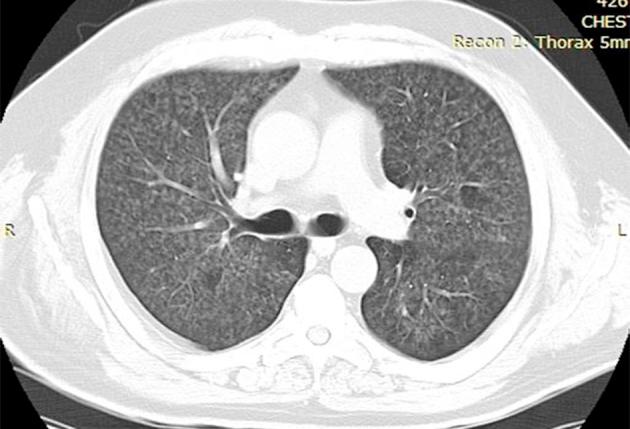

A 55-year-old Caucasian man, with a six-month medical history of UC under long-term maintenance treatment with oral mesalazine, presented with a week-long low-grade fever, dry cough and a diffuse bilateral centrilobular ill-defined micronodular pattern in chest imaging. On examination, he had dyspnea with hypoxemic respiratory failure. After extensive workup, potential differential diagnoses such as pulmonary infections were ruled out. Bronchoalveolar lavage (BAL) cellular analysis demonstrated a predominance of lymphocytes and an eosinophilia. The transbronchial biopsy findings confirmed lymphocytic alveolitis. The diagnosis of subacute HP was made with confidence because of the compatible clinical, radiographic, physiologic, BAL and histopathologic findings. Mesalazine withdrawal was decided. Substantial clinical improvement was promptly noticed. The fever abated within 24 hours alongside with a significant improvement of arterial oxygen saturation and lung function parameters. A radiological recovery was also gradually noticed.

一名55岁的白人男性,有6个月的UC病史,长期口服美沙拉嗪进行维持治疗,出现了持续一周的低热、干咳,胸部影像学显示双侧弥漫性小叶中心性边界不清的微小结节影。检查时,他有呼吸困难伴低氧性呼吸衰竭。经过广泛检查,排除了肺部感染等潜在的鉴别诊断。支气管肺泡灌洗(BAL)细胞分析显示淋巴细胞占优势且有嗜酸性粒细胞增多。经支气管活检结果证实为淋巴细胞性肺泡炎。由于临床、影像学、生理学、BAL和组织病理学结果相符,确诊为亚急性HP。决定停用美沙拉嗪。很快就注意到临床有显著改善。发热在24小时内消退,同时动脉血氧饱和度和肺功能参数有明显改善。影像学上也逐渐恢复。